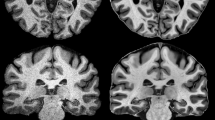

Segmentation of human brain using structural MRI is a key step of processing in imaging neuroscience. The methods have undergone a rapid development in the past two decades and are now widely available. This non-technical review aims at providing an overview and basic understanding of the most common software. Starting with the basis of structural MRI contrast in brain and imaging protocols, the concepts of voxel-based and surface-based segmentation are discussed. Special emphasis is given to the typical contrast features and morphological constraints of cortical and sub-cortical grey matter. In addition to the use for voxel-based morphometry, basic applications in quantitative MRI, cortical thickness estimations, and atrophy measurements as well as assignment of cortical regions and deep brain nuclei are briefly discussed. Finally, some fields for clinical applications are given.